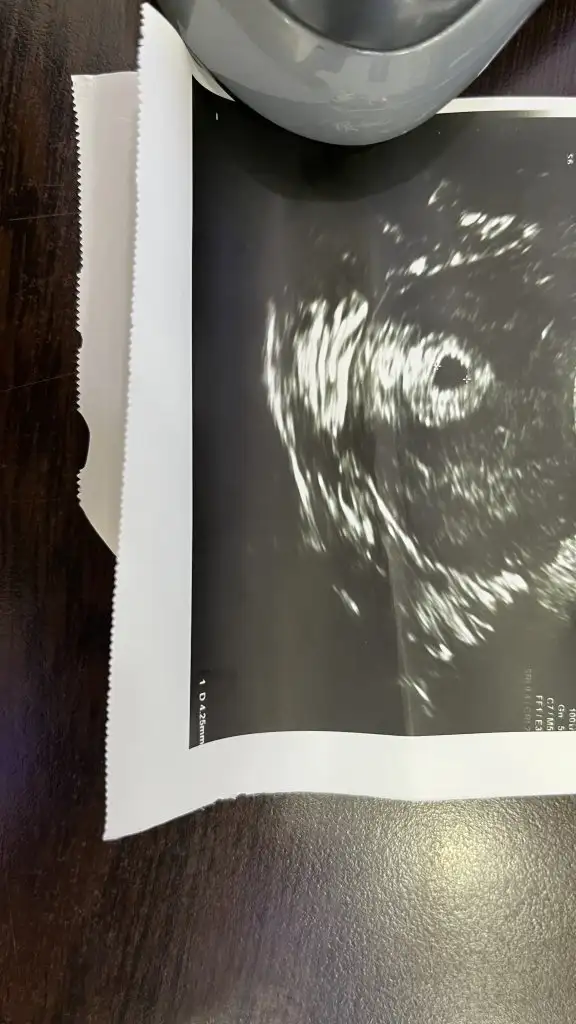

Kızlar merhaba sag tarafımda sancı ile uyandım kendi doktorum sehir dısında oldugu için baska bir doktordan randevu alıp gittim transfere göre 4+5 son adete göre 4+2 haftalık görünüyorum doktor baktı keseye burda normal dedi agrıların olabilir dedi ve gönderdi yolk kesesi falan hiç bişe demedi kese boyutunuda demedi ultrason kagıdından anlayanlar bakabilir mi

Köşede yazıyor 4.25 mm kese ölçünüz haftasıyla uyumlu